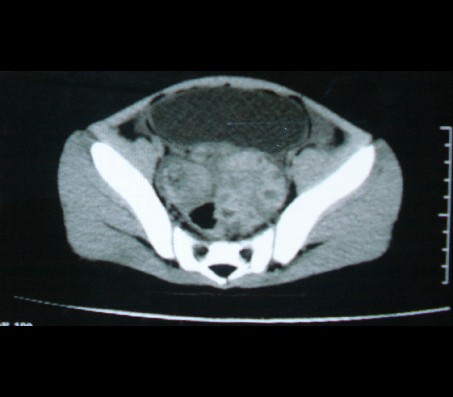

标题: PED0942:女性,8岁,B超提示盆腔病变,请会诊! [打印本页]

标题: PED0942:女性,8岁,B超提示盆腔病变,请会诊!

畸胎瘤

考虑畸胎瘤可能性大!

建议增强进一步检查除外畸胎瘤。

考虑畸胎瘤可能。

考虑畸胎瘤可能

考虑畸胎瘤可能性大.

考虑畸胎瘤可能性大。

畸胎瘤可能性大。

畸胎瘤可能性大!

考虑畸胎瘤可能大,建议进一步检查。